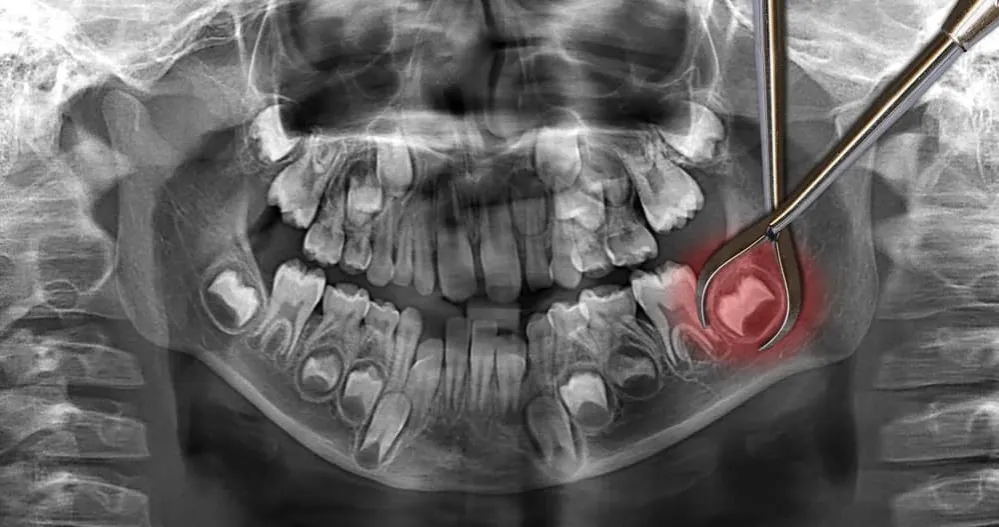

Po usunięciu ósemki: czy L4 to standard?

Usunięcie zęba, zwłaszcza tak skomplikowane jak ekstrakcja zatrzymanej ósemki, to często poważny zabieg chirurgiczny. Nie jest niczym niezwykłym, że po takim zabiegu pacjent odczuwa silny ból, ma opuchliznę, a nawet problemy z otwieraniem ust czy jedzeniem. W takich sytuacjach, kiedy ból poekstrakcyjny i ogólne złe samopoczucie uniemożliwiają normalne funkcjonowanie i wykonywanie pracy, zwolnienie lekarskie jest w pełni uzasadnione. Okres rekonwalescencji może trwać od kilku dni do tygodnia, a moim zadaniem jako lekarza jest zapewnienie pacjentowi komfortu i czasu na powrót do zdrowia.Leczenie kanałowe, implanty i chirurgia szczękowa a niezdolność do pracy